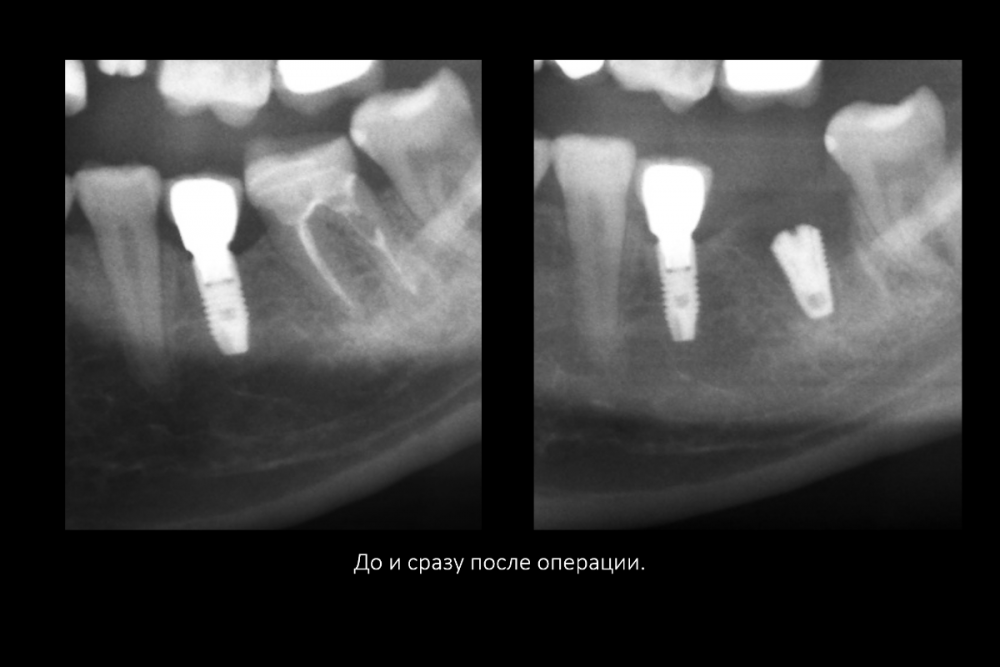

Карен Аванесов Опубликовано 16 июля, 2021 Поделиться Опубликовано 16 июля, 2021 Вариант герметизации послеоперационной раны, когда, хочется установить имплантат и сократить для пациента сроки реабилитации. Итак, "Астра" отличные имплантаты при хороших условиях работают, при экстремальных ситуациях выбор калибров сильно страдает и суживает возможности оператора (очевидно менеджерам не интересно будущее системы, эксклюзивная цацка профайл и маркетинговое продвижение на "озоне" это не то), как по мне, раздутый, абсолютно не удобный хирургический набор, не разделяю восторгов относительно эксклюзивности и предписуемым волшебным свойства, кость наросла! это только на "астре" так или только на анкилозе! На любой системе можно получать результаты. Представляю клинические случаи с одинаковыми условиями, но разными системами, там где "астра" не захотела первичной стабильности, в виду недостаточно широкой талии, "дентиум" диаметром 6мм встал бы на ура, но "астра" такой заказ ортопеда. 8 1 1 3 Ссылка на комментарий

Карен Аванесов Опубликовано 21 февраля, 2022 Автор Поделиться Опубликовано 21 февраля, 2022 Дозрела костна ткань. Возвращаясь к вопросу о "волшебстве" брендовых систем.... Безусловно, молодому специалисту, через сопливый нос бубнить на консультации что от СТАВИТ страуманн, мобель или аштру, поднимает самомнение, окрыляет, иногда и до звездной болезни, помогает быстрее "заматереть,"но сути не меняет. Кость "подрастает" не только аштре например, что иногда демонстрируют с восторгом, но и на отстойном дентиуме тоже, и думаю и на отстойной альфа-био и т.д., т.е. все-же от условий зависит, пациента и конечно техника, что там как и дальше будет. Соберу кейс покажу вошебный рост на голых витках корейского народного ширпотреба)))) 1 Ссылка на комментарий